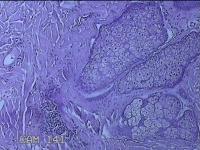

头皮结节

性别

男

年龄

33岁

临床诊断

皮肤赘生物

一般病史

发现头皮结节半个月余,无明显疼痛及不适。

标本名称

大体所见

灰白暗红色带皮肤样结节1x0.8x0.3cm一个,表面糜烂,切开结节呈实性,切面灰白粉红色,质软。

图3